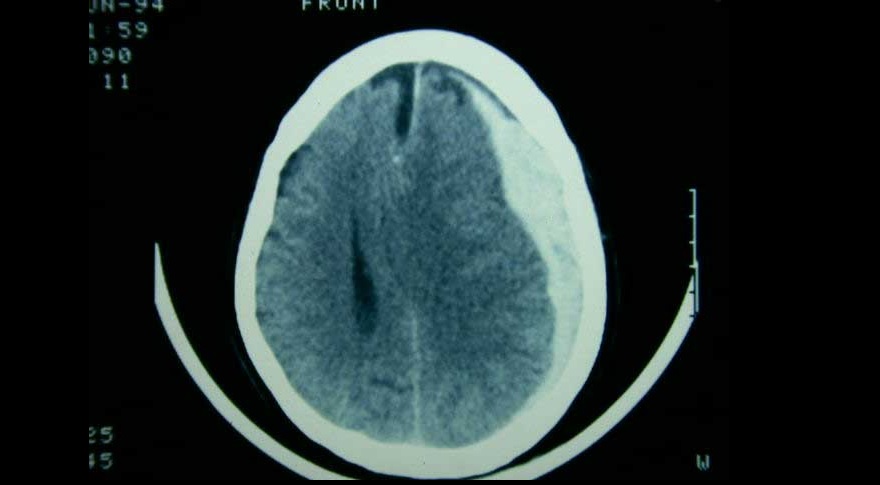

Tres ensayos clínicos exploran la utilidad de la embolización de esta arteria en el manejo del hematoma subdural subagudo o crónico, con miras a reducir la tasa de recurrencias y la necesidad de nuevas intervenciones. New England Journal of Medicine, 20 de noviembre de 2024.